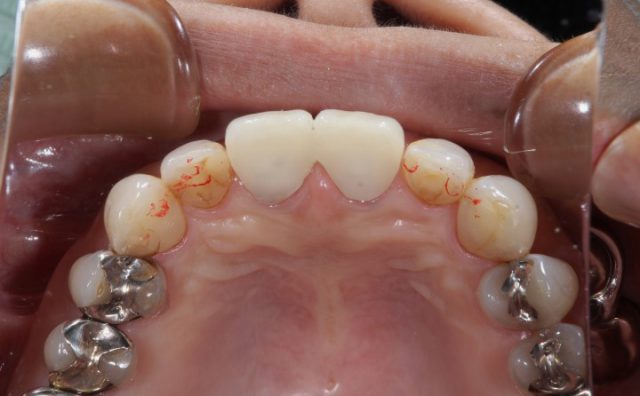

施術前

施術前の画像を見るとそれほど変色している印象を受けることはありませんが、よく見ると前歯の虫歯治療した後の部分の詰め物の変色しています。今回の患者様はこの部分をとても気にされていました。

詰め物を削りやり直したとしてもまた数年後には同じことになるため今回は思い切ってオールセラミックによる施術を選択されました。